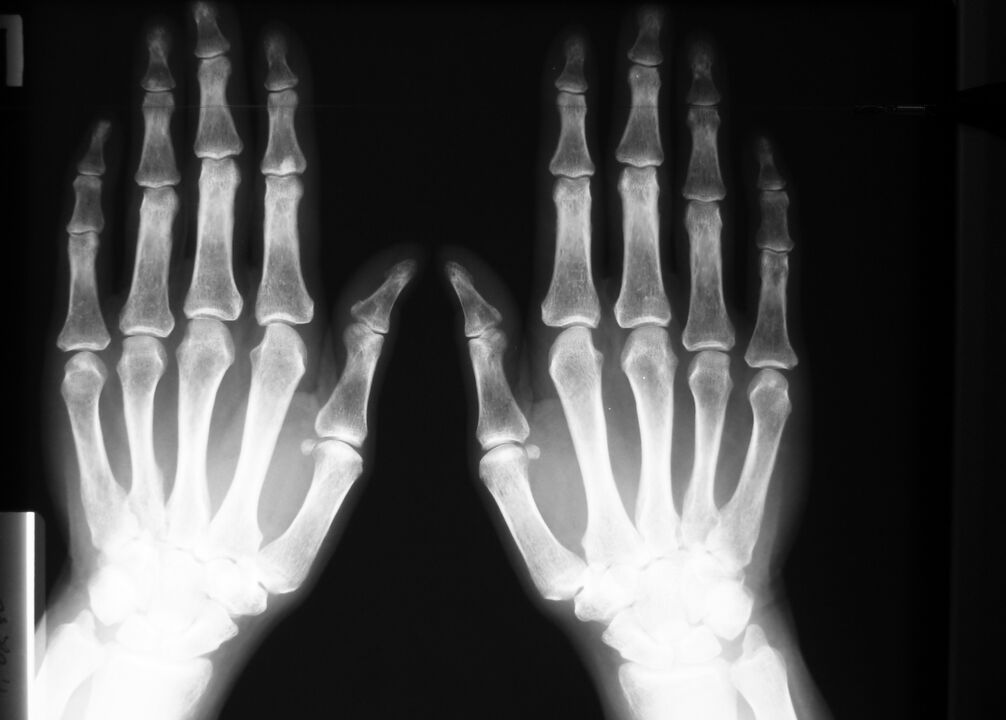

Pour les maladies dégénératives et les blessures – modifications des articulations : tissu osseux et cartilage, visibles sur les radiographies ou les résultats de tomodensitométrie.

L'IRM donnera également une image complète des modifications des tissus mous en cas d'inflammation du tendon, en cas de rupture d'un ligament ou d'un muscle.